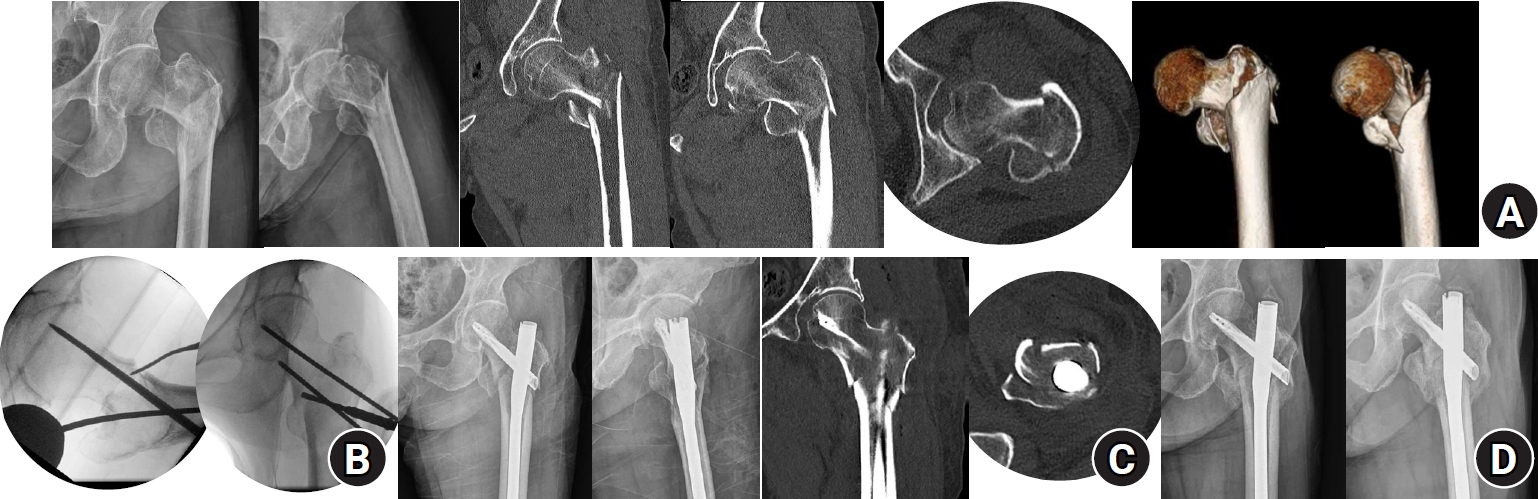

Fig. 4.

Computed tomography (CT) images of the anteromedial cortical support states in intertrochanteric femur fractures. The upper row shows coronal CT images illustrating medial cortical support, and the lower row shows axial CT images illustrating anterior cortical support. (A) Positive cortical support; (B) neutral cortical support; (C) negative cortical support. The red arrow indicates the anteromedial cortical state.

jmt-2025-00311f4.jpg

Axial CT images were used to evaluate anterior cortical support, which was classified as positive, neutral, or negative. When the anteromedial cortex of the proximal segment was located anterior to that of the distal segment, anterior cortical support was classified as positive. When both cortices were aligned, it was classified as neutral. When the proximal cortex was located posterior to the distal cortex, it was classified as negative. Coronal CT images were used to assess medial cortical support. This was also classified as positive, neutral, or negative. When the anteromedial cortex of the proximal segment was located medial to that of the distal segment, medial cortical support was classified as positive. When both cortices were aligned, it was classified as neutral. When the proximal cortex was located lateral to the distal cortex, it was classified as negative (Fig. 4). These assessments were performed on both preoperative and postoperative CT scans. Postoperative AMCS status was evaluated as an outcome of the percutaneous anterior leverage technique and was included in the treatment failure risk factor analysis. It was also compared with the preoperative status in each patient to assess the changes resulting from the use of the technique. In addition, we performed subgroup analyses based on patient demographics and fracture characteristics (AO/OTA classification and Dorr type), reporting the postoperative AMCS within each subgroup. Complications such as femoral artery injury associated with the percutaneous anterior leverage technique were also assessed.